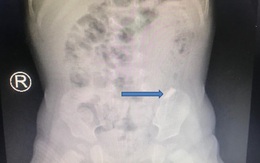

TTO - Ngay khi nuốt mảnh kiếng vỡ vào bụng, bé trai 10 tháng tuổi khóc ói liên tục, chảy máu miệng. Kết quả hình ảnh X-quang thấy dị vật di chuyển trong đường tiêu hóa, việc nội soi gắp dị vật khá khó khăn vì nguy cơ thủng ruột, dạ dày, thực quản...